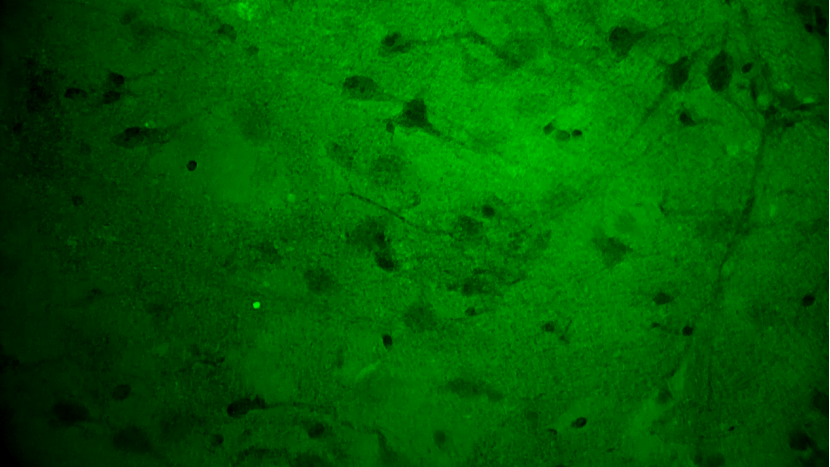

術(shù)中EndoSCell?細胞圖像如下:

手術(shù)切緣處發(fā)現(xiàn)的正常腦白質(zhì):細胞核形態(tài)正常,密度低且分布均勻